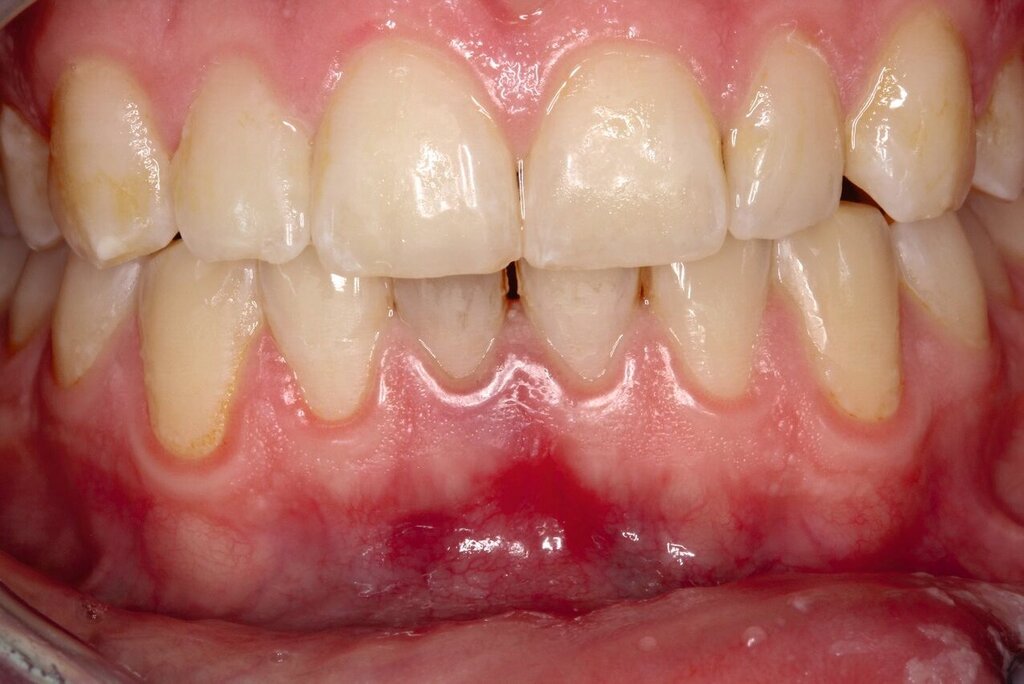

Zusätzlich zeigten sich ein dunkel-bläuliches Hämatom sublingual in Regio 32 bis 42 und ein korrespondierendes Hämatom im Vestibulum zwischen den Zähnen 31 und 41 (Abbildungen 1 und 2). Beide schienen mit der extraoralen Kinnwunde zu korrelieren und waren auf Palpation schmerzhaft. Es konnten keine Stufen ertastet und keine Krepitation wahrgenommen werden (Flowcharts Abbildungen 13 und 14).

Nach einem Monat stellte sich der Patient für eine klinische und röntgenologische Nachkontrolle vor (Abbildungen 8 und 9). Nach der operativen Frakturversorgung hatte sich die Okklusion normalisiert und die Bewegung des Unterkiefers war weder schmerzhaft noch eingeschränkt. Die Zähne 41 und 42 zeigten einen Lockerungsgrad I und reagierten auf Kälte nicht sensibel. Dies erhärtete den Verdacht auf eine Dislokationsverletzung mit begleitendem Pulpainfarkt als Folge des Sturztraumas.